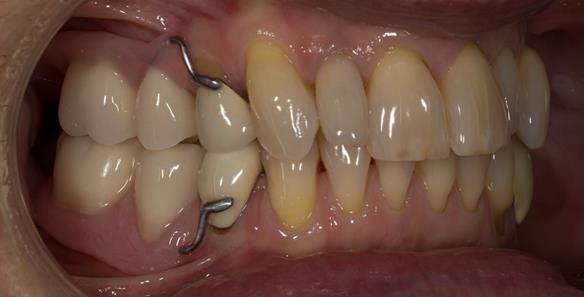

This newsletter describes in step by step detail Angela's transition through immediate partial dentures to crown supported definitive metal based dentures.

This 58 year old woman was referred to me by her general dental practitoner for treatment.

- Generalised Periodontitis; Stage 4, Grade C, Currently Unstable. Risk Factors: Type 1 diabetes. 16, 17 - hopeless prognosis. 14, 24, 26, 27, 34, 37, 44 - guarded prognosis

- Poor marginal fit and poor appearance of crowns and bridgework

- Yellowing teeth

The clinical situation and treatment process is shown in detail below with photographs. I (Finlay Sutton) provided the clinical work and Rowan Garstang provided the technical work.